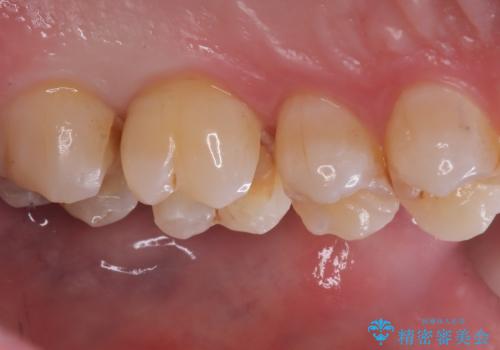

左上6番の歯には元々修復物が入っていましたが、それも一度除去し新たにMOD窩洞のセラミックインレーをセットしました。

左上7番咬合面裂溝の着色部分は今後エアフロー等を使用し落としていく予定です。

セラミックインレーセット時はラバーダム防湿を行っています。